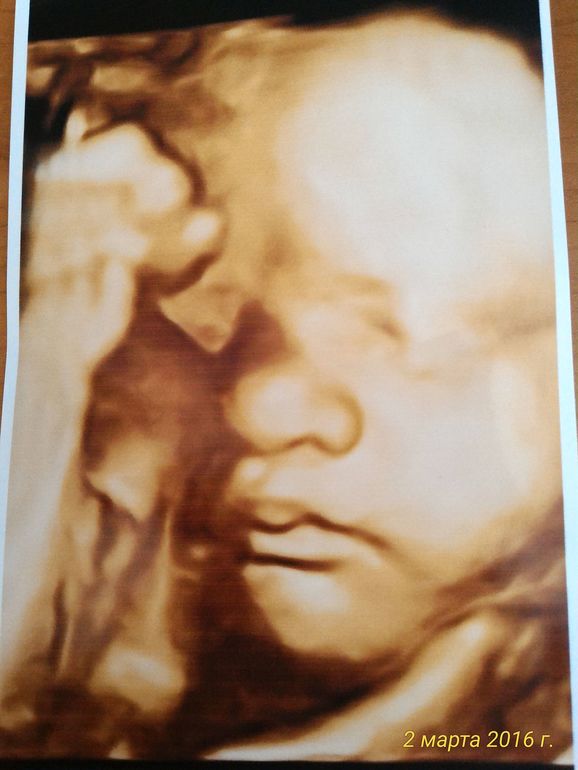

УЗИ 32 недели: повидались с малышкой

УЗИ, КТГ, доплерВ целом всё хорошо у нас: все замеры соответствуют сроку, доплер тоже хороший.)) это радует. Единственное есть неполное однократное обвитие, но это сказали не страшно... Лежит как нужно, головкой вниз. Держала в руке свою стопу! Забавная картина)) Врач ещё акцентировала внимание, что у неё волос много на голове, реально видно было!)) короче, будет что заплетать)) Весит почти 2 кг, средний вес для этого срока. Для меня это и хорошо, лишь бы крупная не была как сын, а то я в родах так намучилась с ним(( Ходили на узи всей семьёй: я, муж и сын. Осталось совсем не долго и скоро мы встретимся с нашей куколкой!))